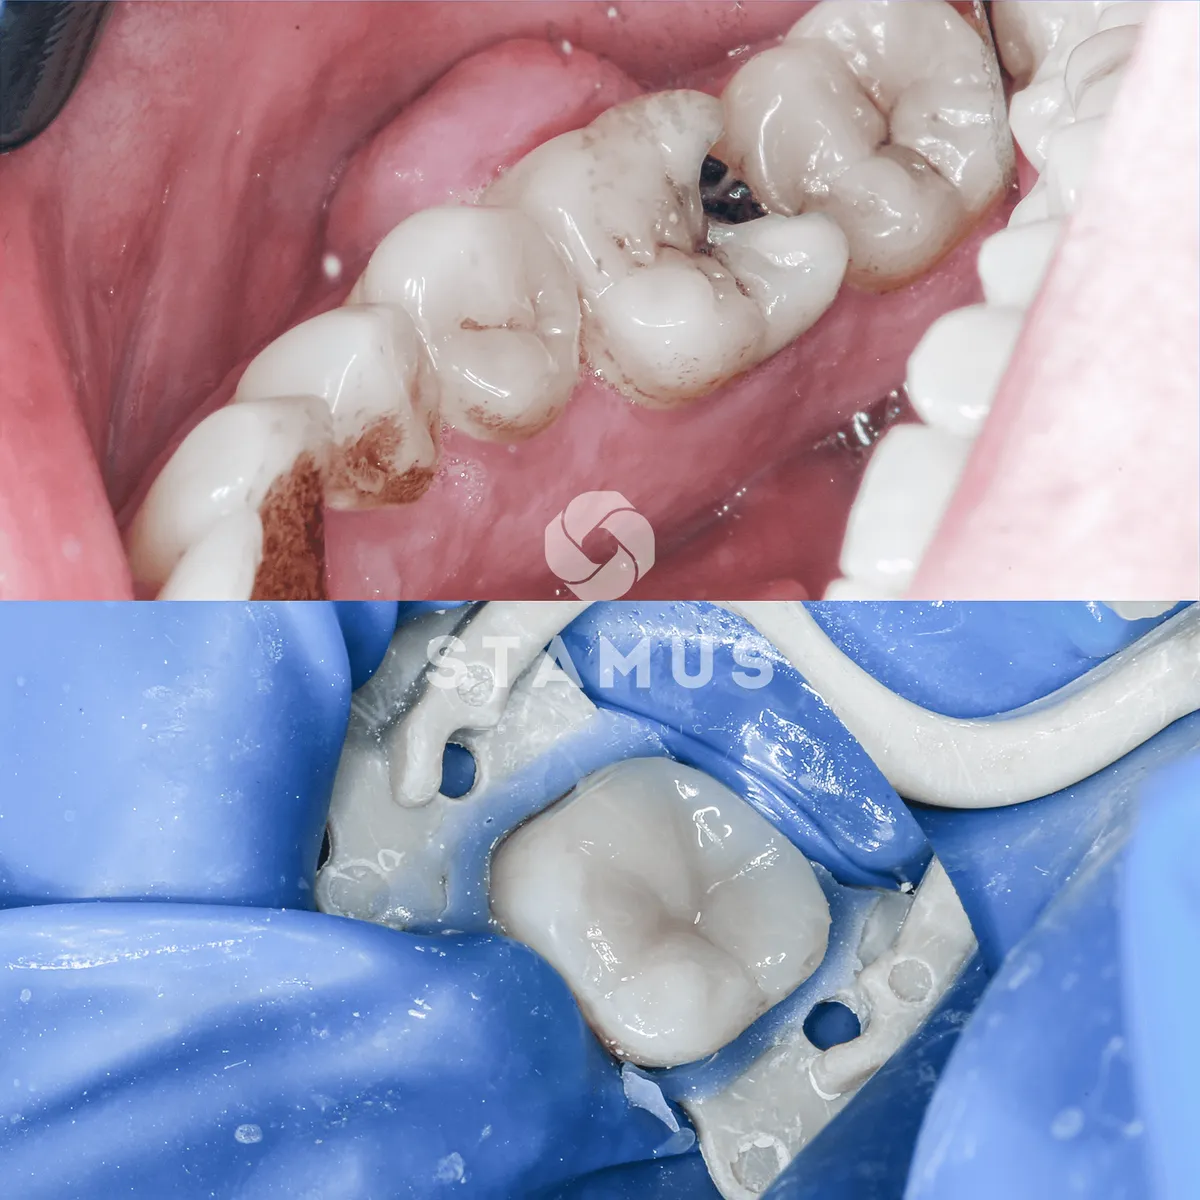

Лечение периодонтита

Симптомы, с которым обратился пациент

Боль в зубе

Отек десны

Проведено эндодонтическое лечение и вскрытие абсцесса за 2 посещения. Рекомендовано покрытие зуб коронкой